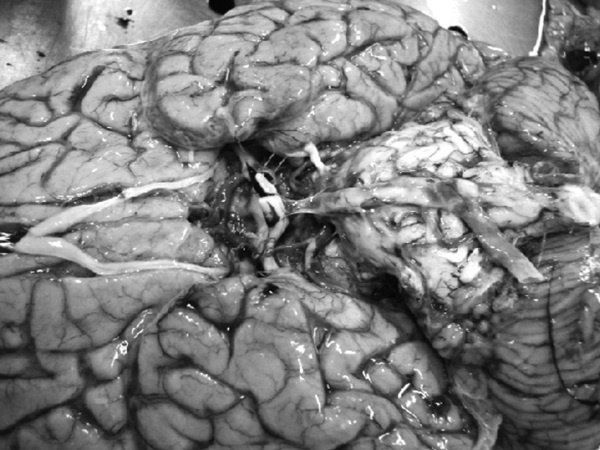

Атеросклероз сосудов головного мозга. Отек головного мозга

Иллюстрация к книге — Маломобильный пациент [i_004.jpg]